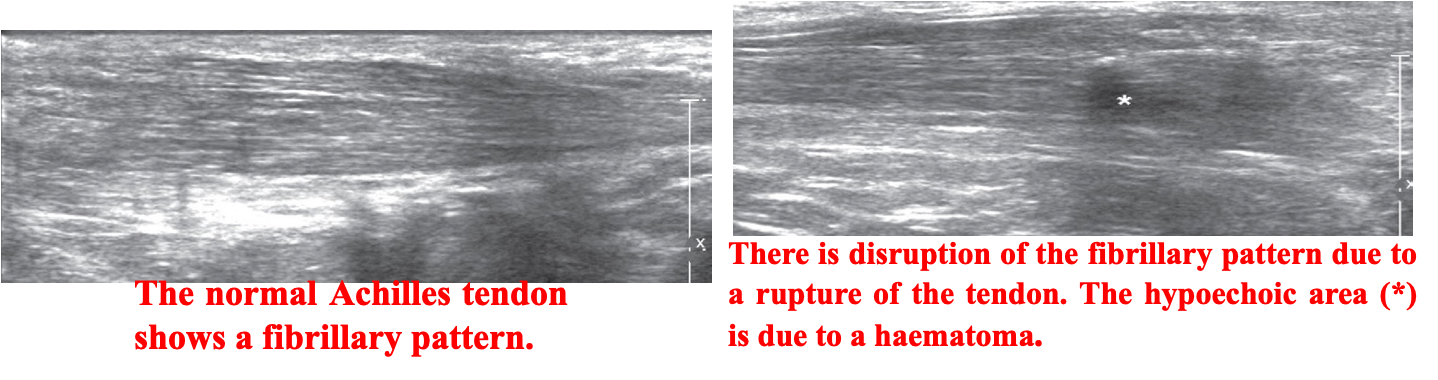

- Detecting tenosynovitis, tendon tears and rupture.